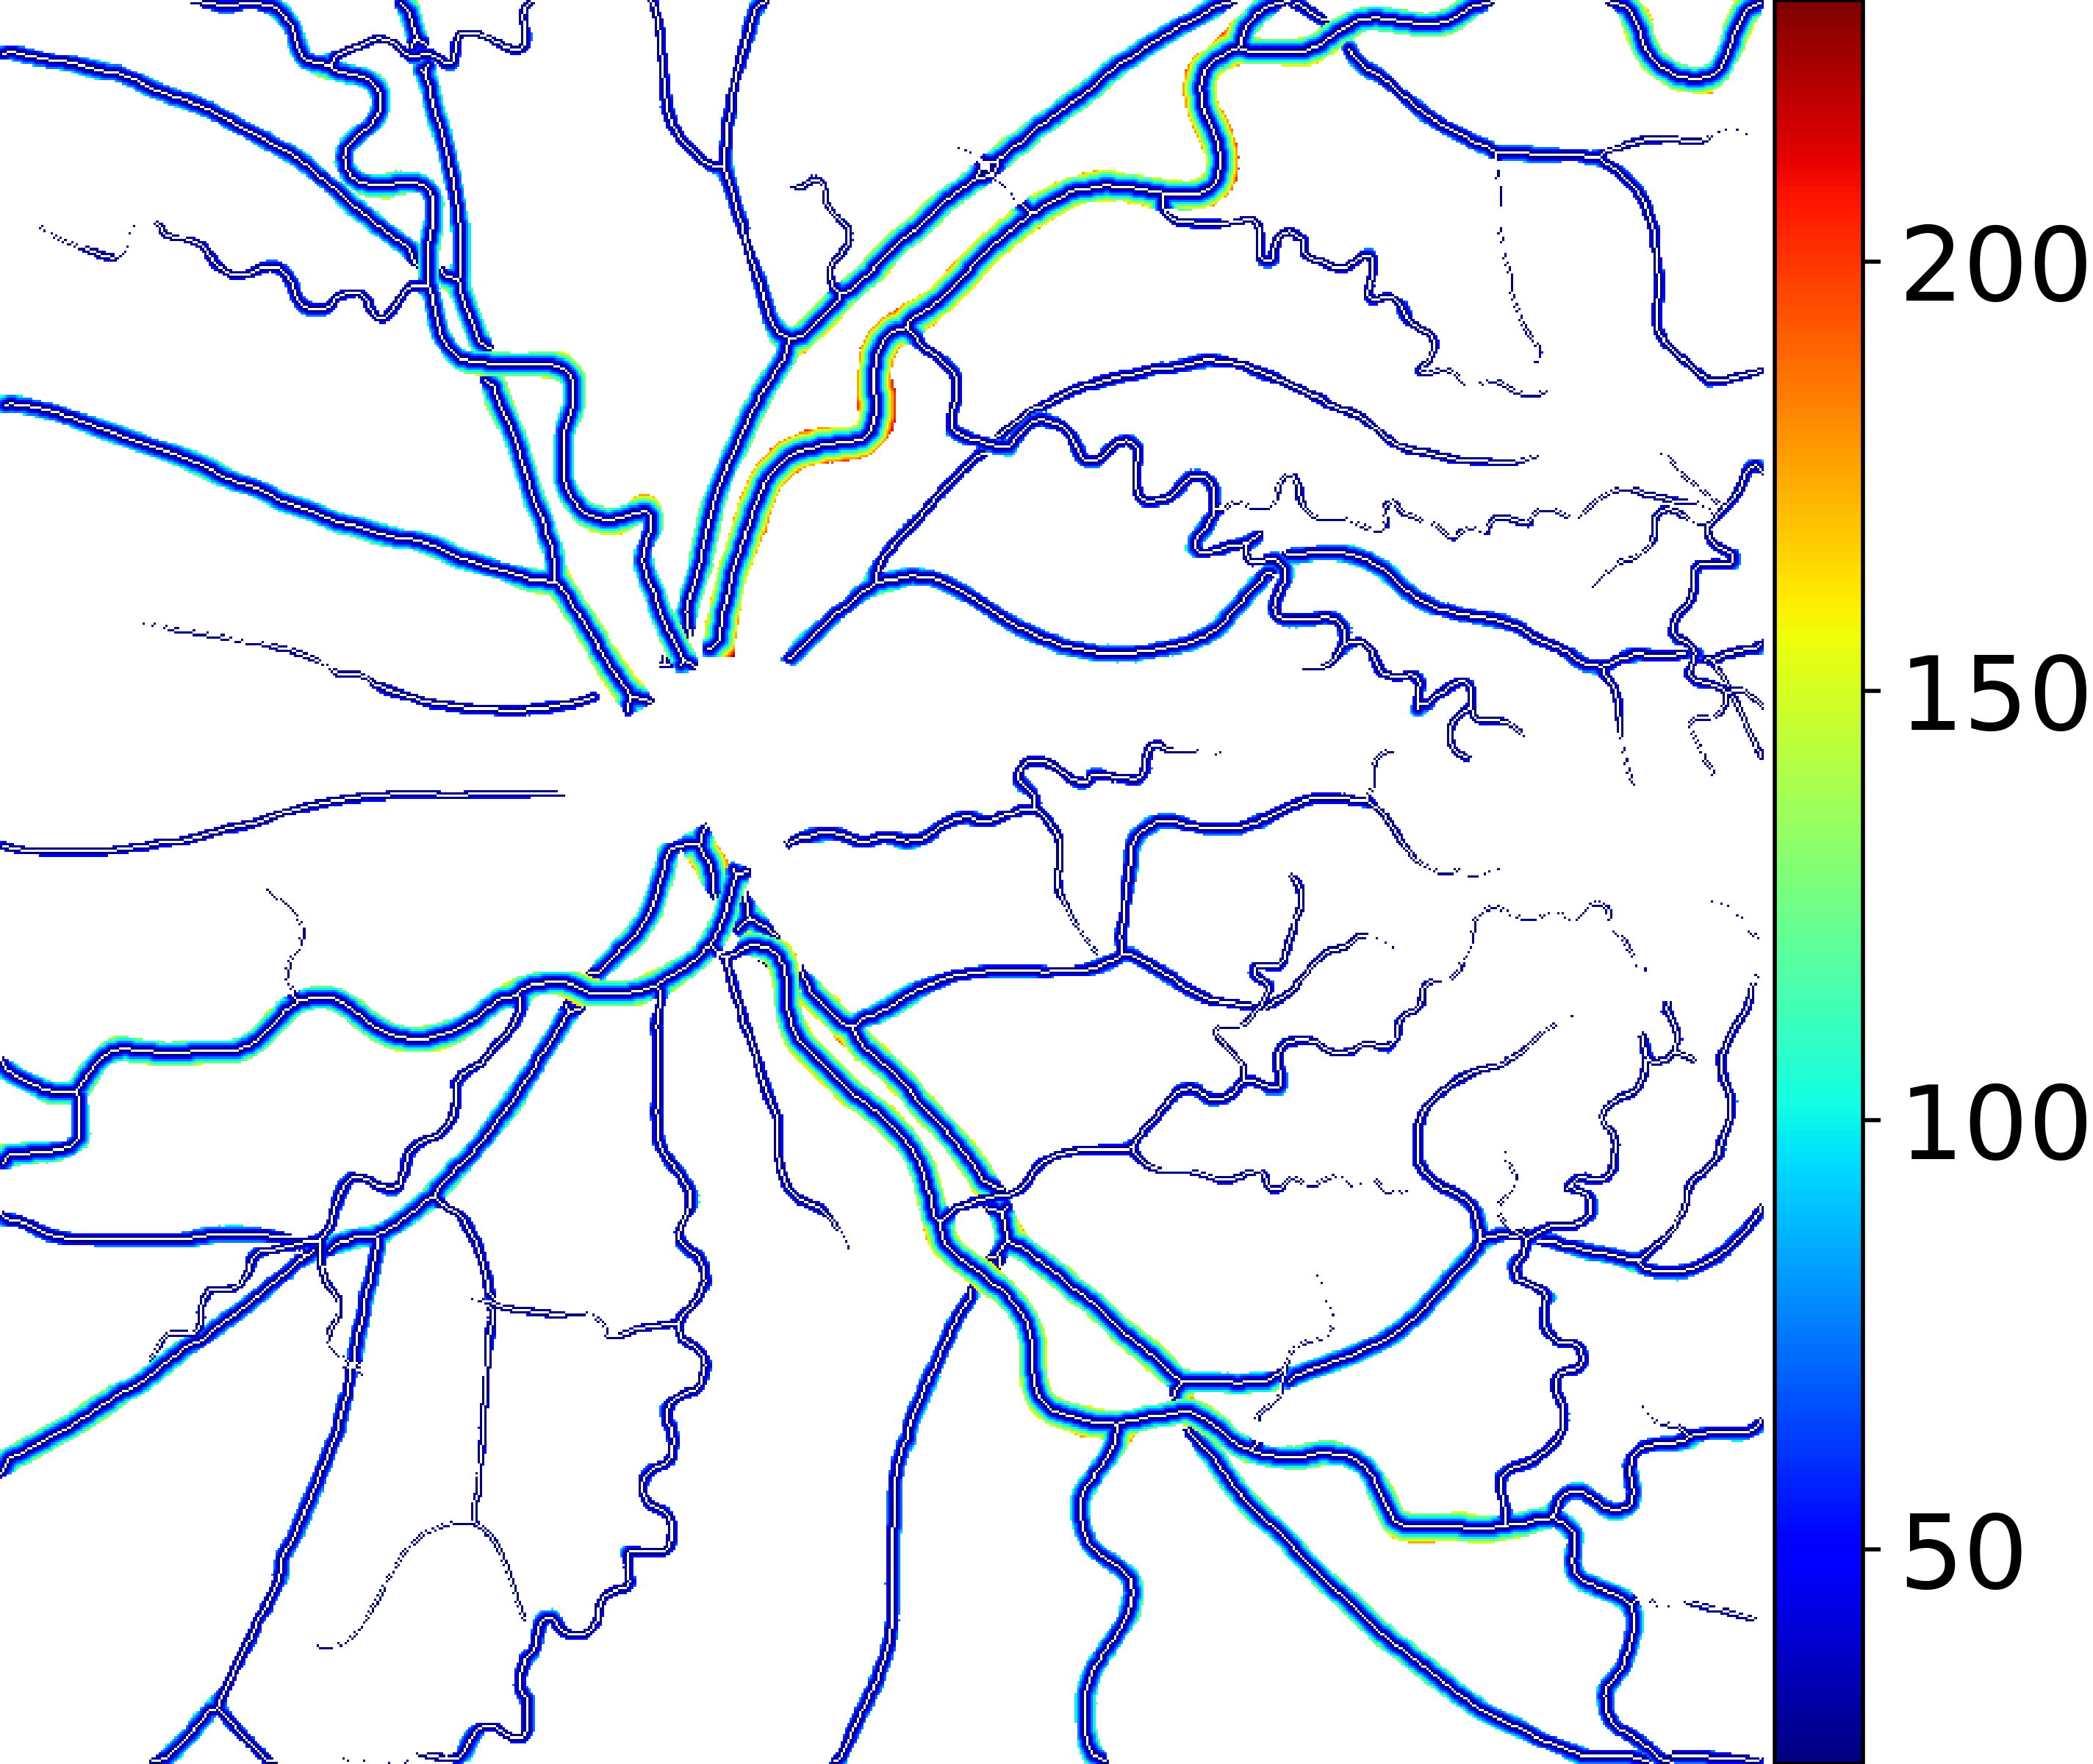

IV-C Vessel Width Estimation

From the segmentation predicted by the SegRAVIR network, our model measures the diameter of the arteries and veins. To this end, the segmentation probability map is first thresholded, using a constant value of 0.5, to obtain the medial curves of the vessels by iteratively identifying and removing border pixels while maintaining vessel connectivity, in an approach similar to the thinning algorithm presented by Zhang et al. [49]. Then, the distance transform of the medial curve mask is multiplied with the segmentation mask in a pixel-wise manner. The result is the diameter distance map with respect to the medial curves of the segmented vessels.

VI-B Vessel Width Estimation

Table VI presents a quantitative comparison of the measured diameters using the segmentation outputs of SegRAVIR and competing approaches. Using the pixel-wise annotated masks, the reference average diameter of the arteries and veins in the test set of the RAVIR dataset were measured as and , respectively. According to our analysis, SegRAVIR can accurately measure the diameter of the vessels and it achieves the smallest MAPE among the competing approaches. Specifically, in comparison to CE-Net, Iter-Net, and DU-Net, respectively, SegRAVIR is on average , and more accurate in terms of MAPE for the measured diameter of arteries and , and in terms of MAPE for the measured diameter of veins. Fig. 6 presents qualitative comparisons of reference and SegRAVIR estimated diameter maps.